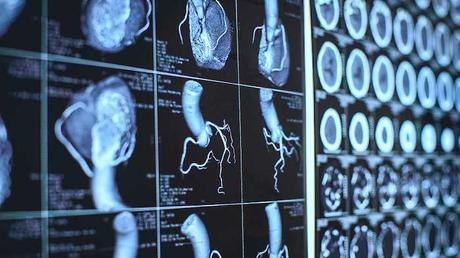

La fibrilación auricular (FA) se considera como la arritmia más común en el mundo. Se cree que FA puede ocurrir tan frecuentemente como en alrededor de 8,9 por 1000 mujeres y 11,5 por 1000 hombres en cualquier momento dado en una población y la frecuencia de esta enfermedad aumenta con la edad. En el 70 por ciento de los casos, FA es causada por enfermedades cardíacas orgánicas crónicas, como la enfermedad cardíaca valvular, , hipertensión y cardiomiopatías dilatadas.

Los músculos cardíacos sensibles cambian gradualmente su estructura después de ocuparse de patologías crónicas y esto puede afectar drásticamente el flujo eléctrico a través del corazón y cambiar la forma en que su corazón late. En 2 de cada 3 pacientes FA, estas arritmias se describen como ” perjudiciales para sus vidas”. El estándar de atención para esta condición ha sido tradicionalmente estratificado en dos ramas de la terapia:

La cirugía de ablación de catéter cardíaco se está convirtiendo rápidamente en el estándar de oro para el control a largo plazo de FA. Un cirujano cardíaco utiliza electrodos especializados para determinar dónde es una descarga excesiva en el músculo cardíaco y luego quema el músculo para reducir la interferencia en la frecuencia cardíaca.

Las ablaciones cardiacas mejorarán la conducción a través del corazón, pero generalmente requieren cirugías múltiples para tener un impacto sostenido. Un estudio reciente encontró que en 188 pacientes que requirieron cirugía de ablación cardiaca, 139 de ellos todavía tenían arritmias después del primer procedimiento y 90 después del segundo procedimiento. En total, el 91 por ciento de estas recurrencias ocurrieron dentro de los dos años posteriores a la cirugía. En este mismo estudio, sólo 7 pacientes experimentaron cualquier tipo de complicaciones graves después de la operación sin muertes y el 82 por ciento de los pacientes declaró que sus síntomas habían mejorado significativamente.

Como se mencionó anteriormente, la cardioversión es el siguiente paso en la gestión que muchos de estos pacientes tendrán que soportar debido a la naturaleza avanzada de sus síntomas. Esta cirugía implica la colocación de electrodos en el corazón y luego un dispositivo secundario mantendrá el nivel de energía bajo control para prevenir nuevos episodios de FA. En un estudio reciente que se utilizó para determinar la efectividad de la cardioversión, 244 participantes se inscribieron y se encontró que casi el 90 por ciento tenía un retorno a un ritmo cardíaco sinusal normal. Además, el 34 por ciento no requirió intervención adicional en casi 3 años después de la cirugía.